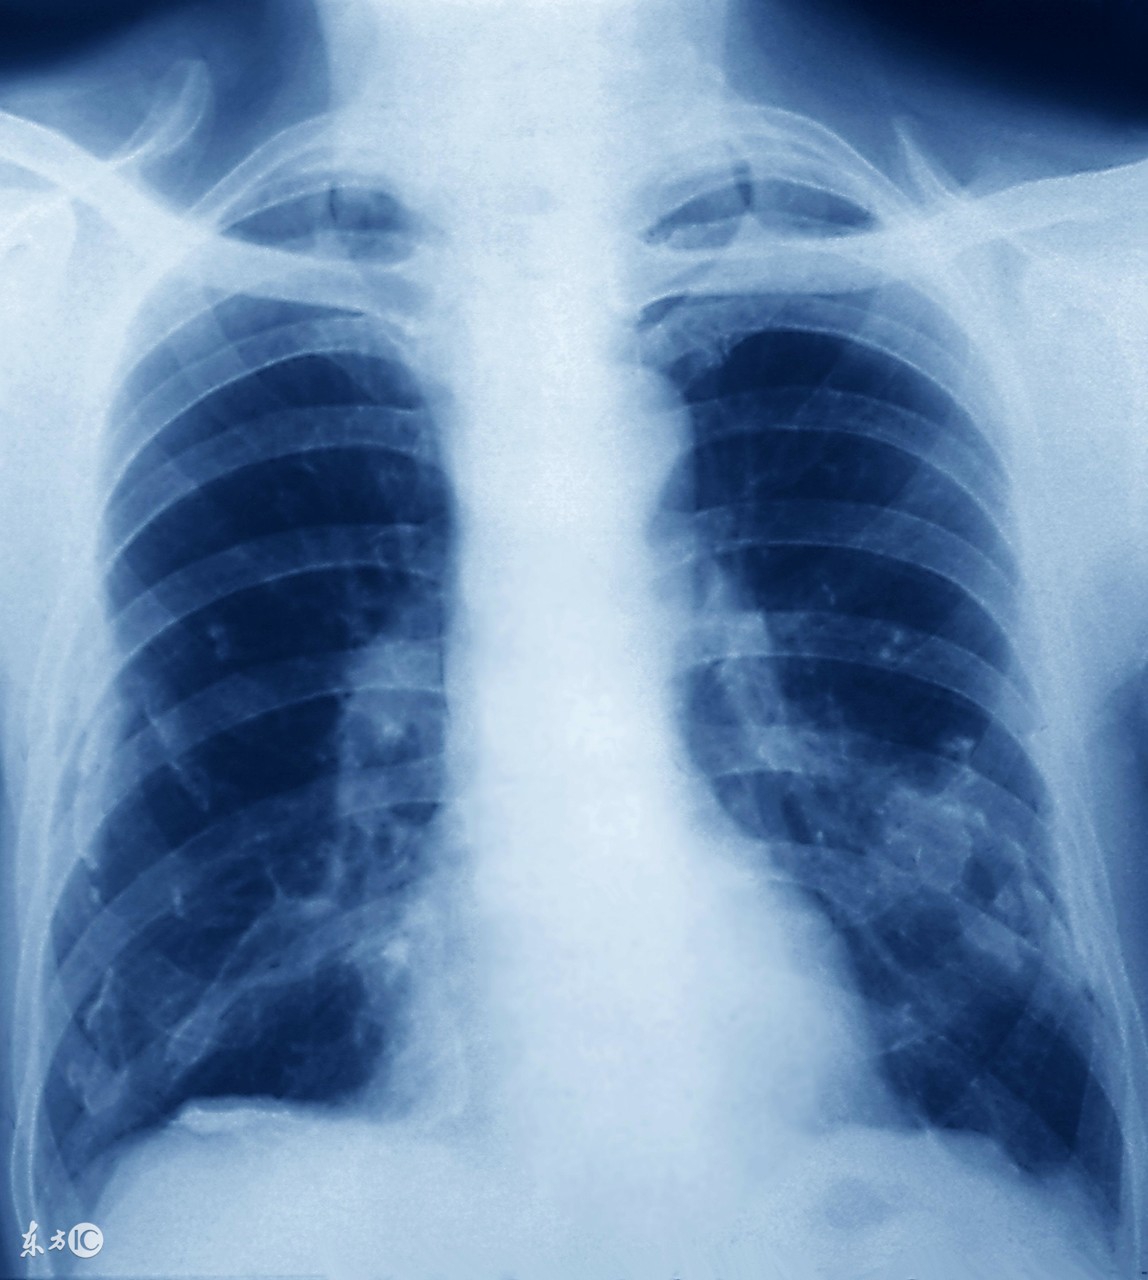

肺结核在现在的生活中已经是很常见的疾病了,对于肺结核的治疗,患者一般离不开药物治疗。药物主要是控制肺结核的病情,降低患者的死亡率。但是用药物治愈肺结核疾病是困难的。下面我们一起来了解怎样可以治愈肺结核。